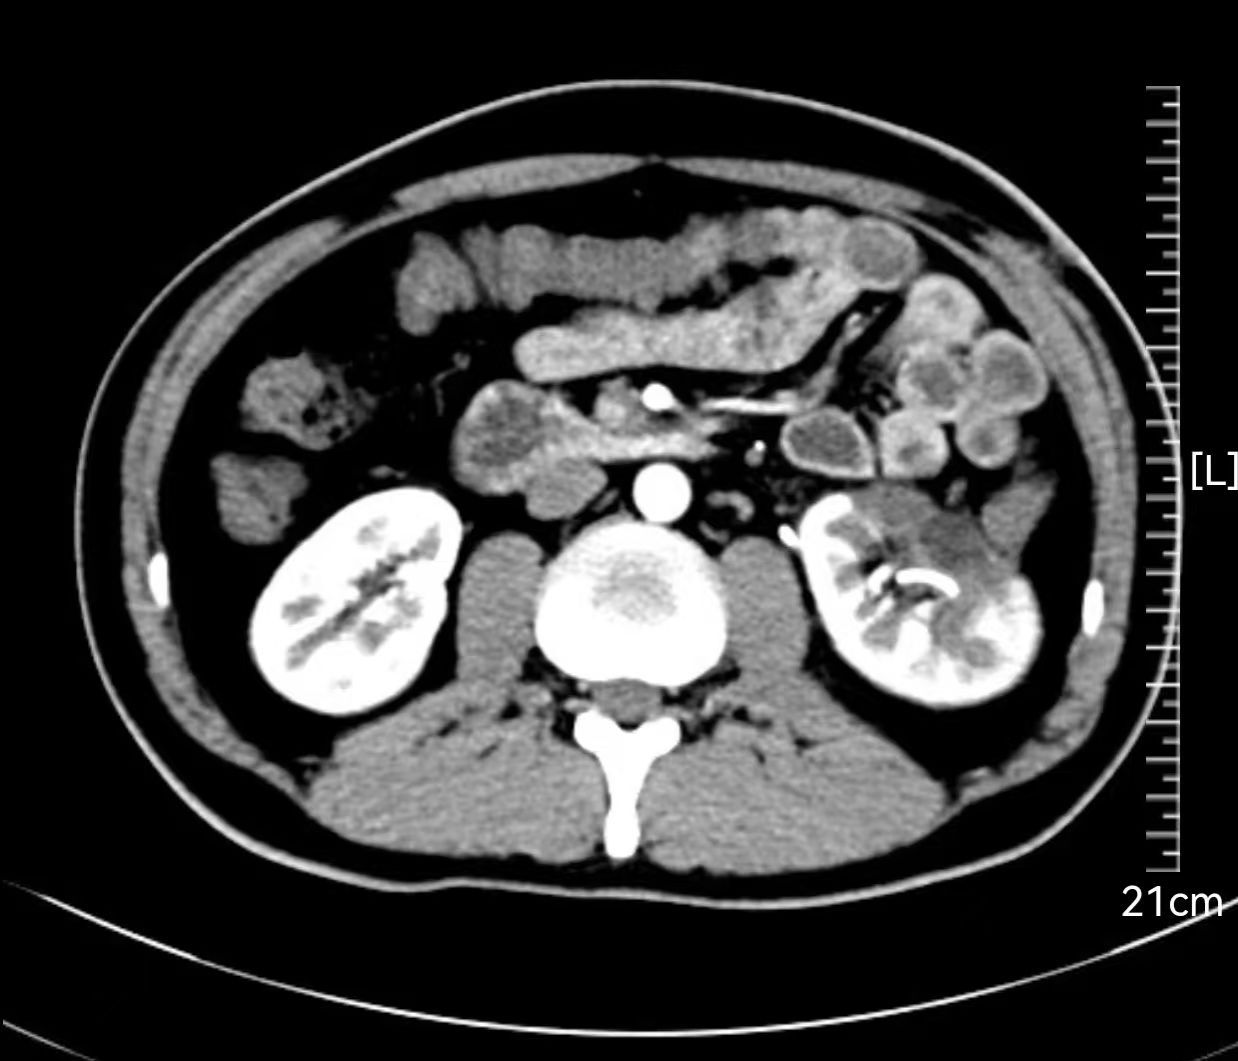

(术后4周复查CT显示肿瘤已被完整切除)

(肾脏形态得到最大限度的保留)